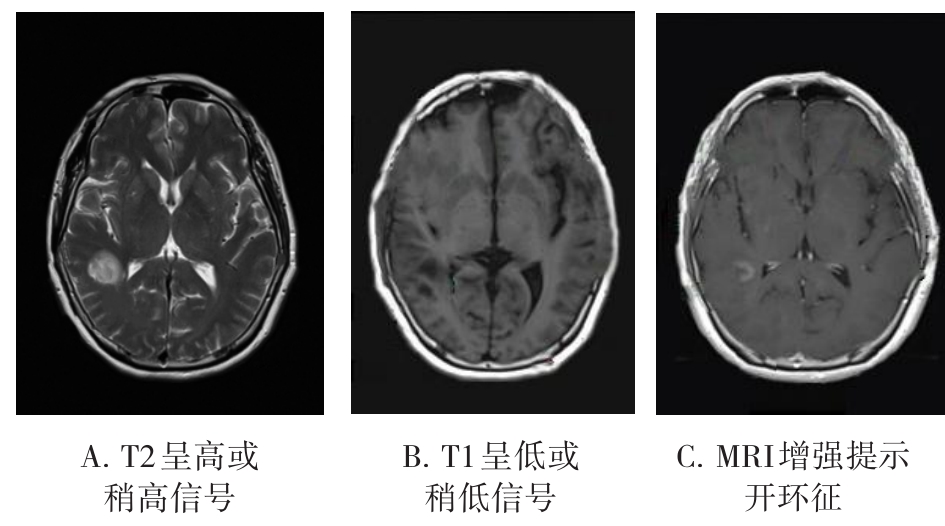

• 肿瘤样脱髓鞘病变报道3例

2023, 48(5):614-617. DOI: 10.13406/j.cnki.cyxb.003183

摘要 (95) HTML (24) PDF 1.29 M (241) 评论 (0) 收藏

摘要: